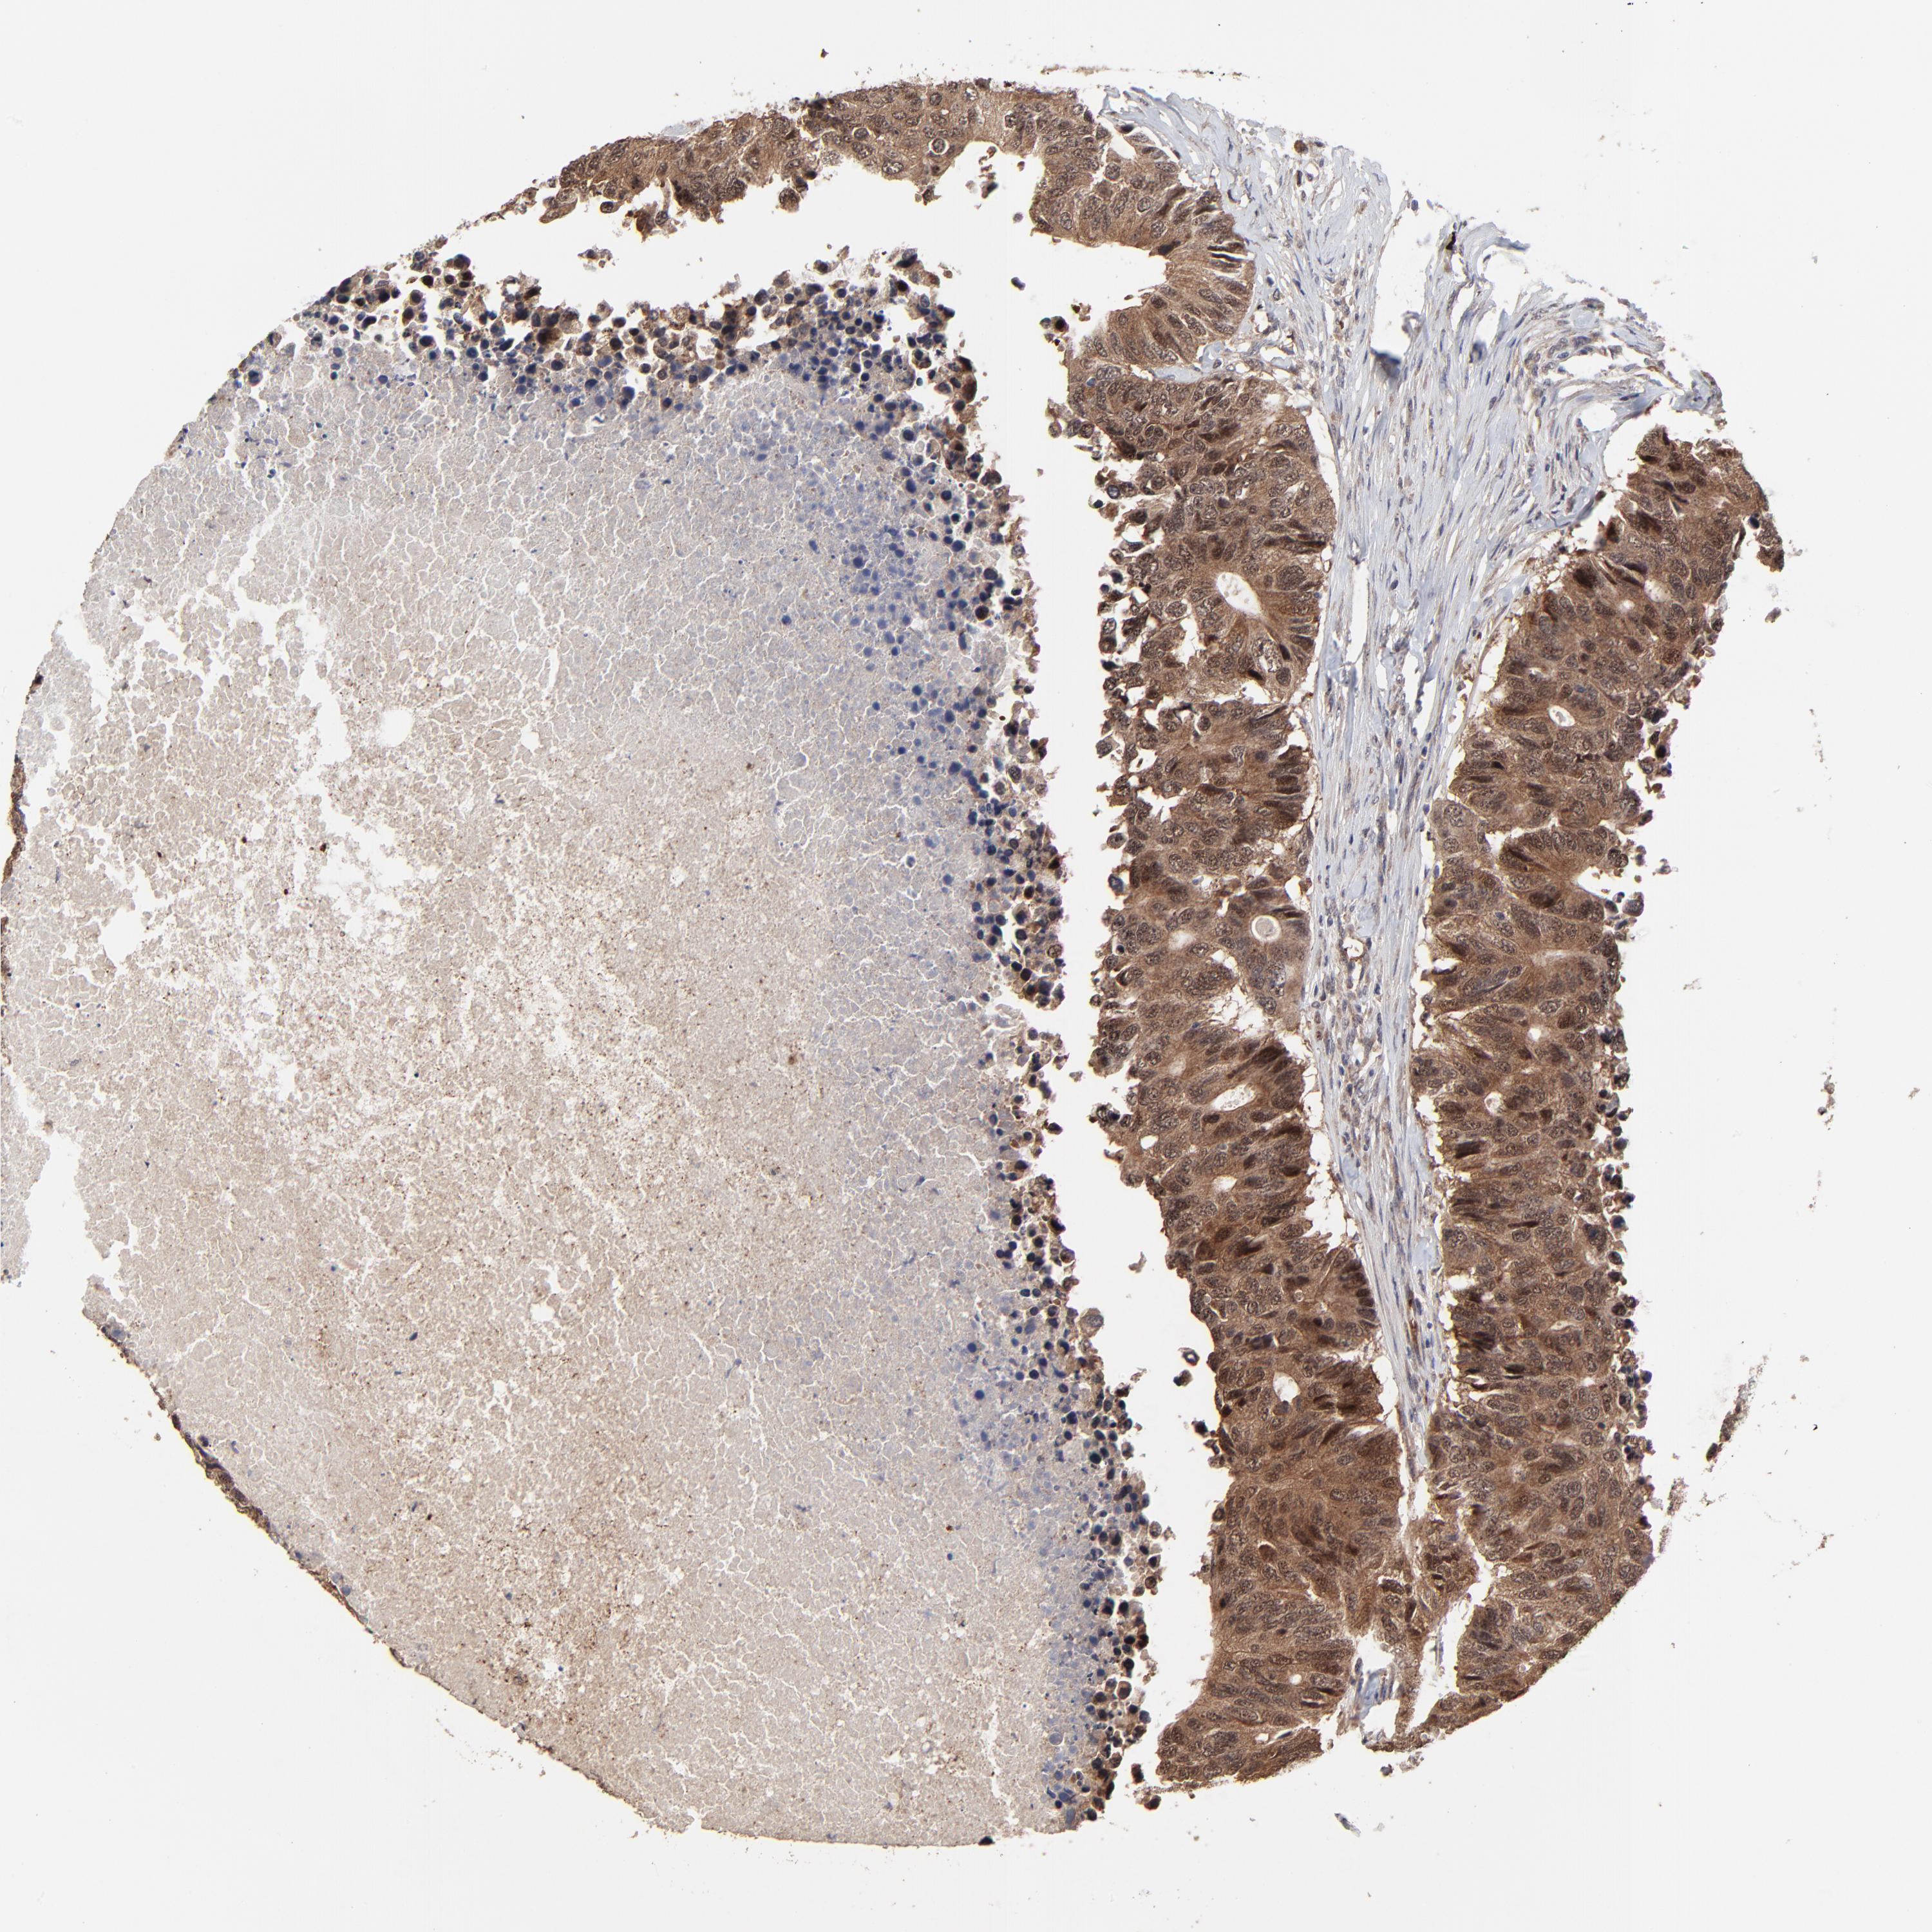

CANCER COLORECTAL CANCER Show tissue menu

Colorectal cancer

Colon adenocarcinoma